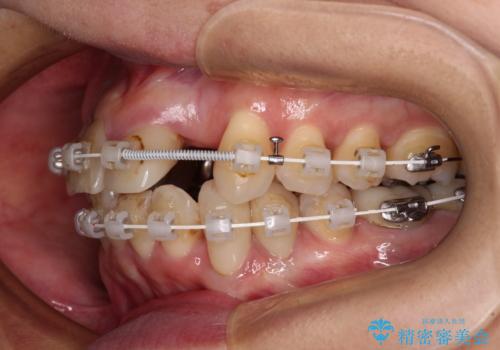

- 非対称な前歯や奥歯の目立つ銀歯を気にして来院された患者様です。

左上前から2番目の歯は、以前裏側に位置していたことから抜歯をされていましたが、前歯の非対称が長年気になっているとのことでした。

矯正治療によって前歯にスペースを作り、左右対称となるようにオールセラミッククラウンにて補綴治療を行うとしました。

他にも奥歯の咬み合わせに問題があったので、全顎的な矯正治療を行い、前歯以外にも口を開けたときに目立つ奥の銀歯をセラミッククラウンにて補綴治療を行うこととしました。